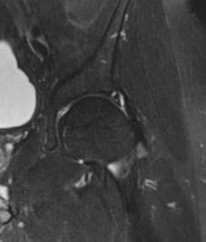

Question 9:

Correct Answer: Anterior cruciate ligament

Explanation:

The radiograph describes a Segond fracture, which is an avulsion fracture of the anterolateral aspect of the proximal tibia. It is typically associated with avulsion of the anterolateral ligament (ALL) or lateral capsular attachments and is highly predictive (pathognomonic) of an anterior cruciate ligament (ACL) tear.